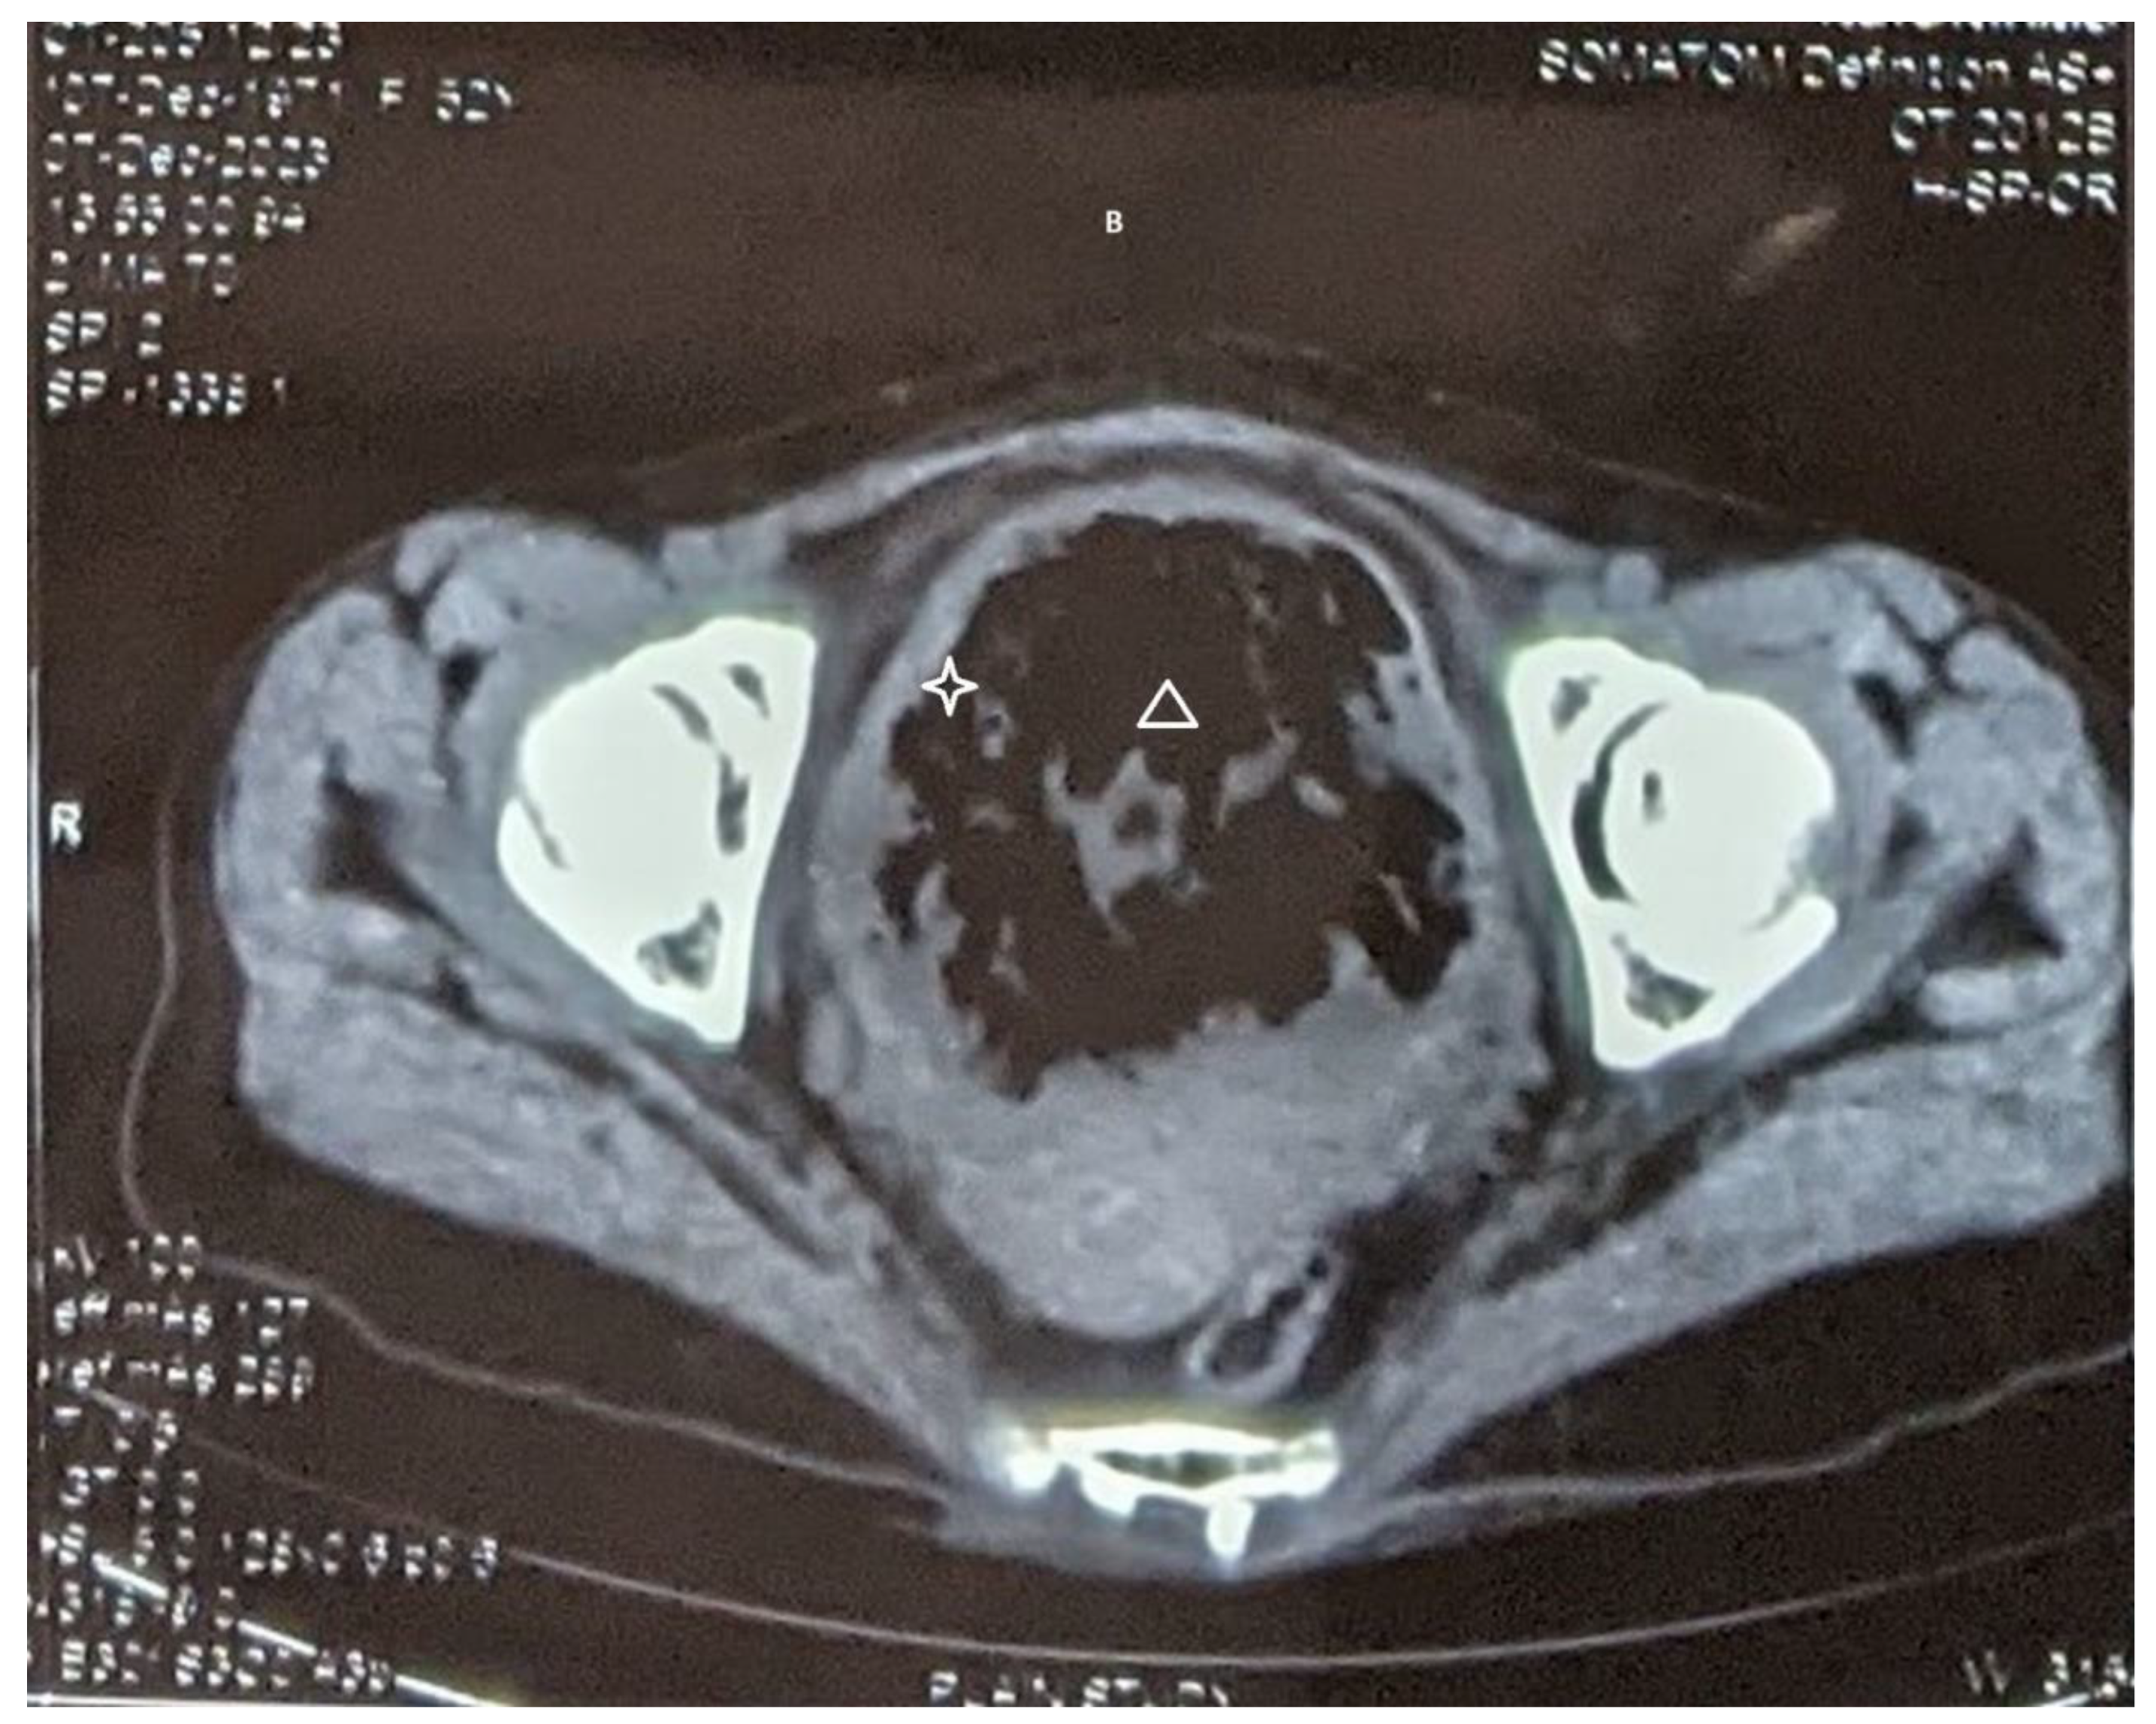

CT scan (non-contrast) detected moderate bilateral hydronephrosis (Figure 1 A), intraluminal gas in urinary bladder with thickened walls indicative of emphysematous cystitis (Figure 1 B). At cystoscopy, a whitish mass filling up the urinary bladder was found. While the mass was being resected with resectoscope (Figure 1C), the mass extruded in toto into the vagina through a vesico-vaginal fistula (Figure 1 D). The histopathological report demonstrated predominantly necrotic material, fungal organism in the form of spores and hyphae. PAS and GMS stain were positive for fungal organism. Ultrasonography repeated after 14 days of Fluconazole showed resolution of hydronephrosis. Patient was scheduled for repair of the fistula but she did not report for the repair.

Figure 1. B: Extensive intraluminal gas in the urinary bladder(triangle) along with thickened wall (star).